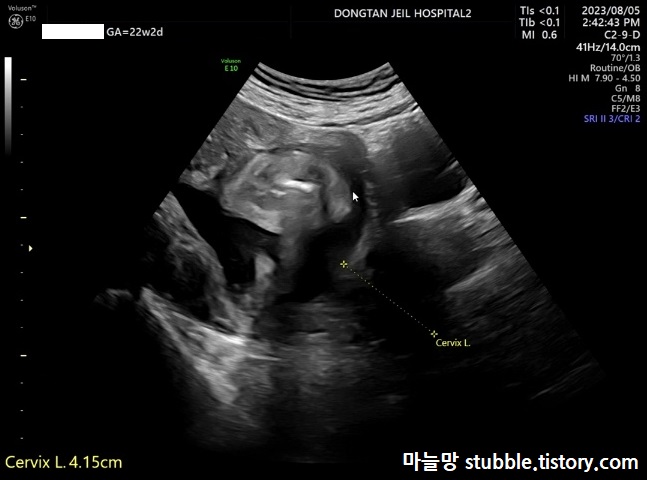

24. 자궁경부 길이 체크 (Cervix L.)

자궁 경부 길이도 체크해 봅니다. 정밀 초음파로 측정한다고 해도 아주 정확하지는 않다고 들었어요. 질초음파로 보는 게 정확한데 2주 전에 질초음파로 측정한것보다 길게 나왔습니다. 2주전에 질초음파로 측정한 수치는 4.02cm / 이번에 측정한 수치는 4.15cm 많은 차이는 나지 않는 것으로 보아서 아직은 자궁경부길이가 안정권에 들어가 있다는 것을 알 수 있어요.